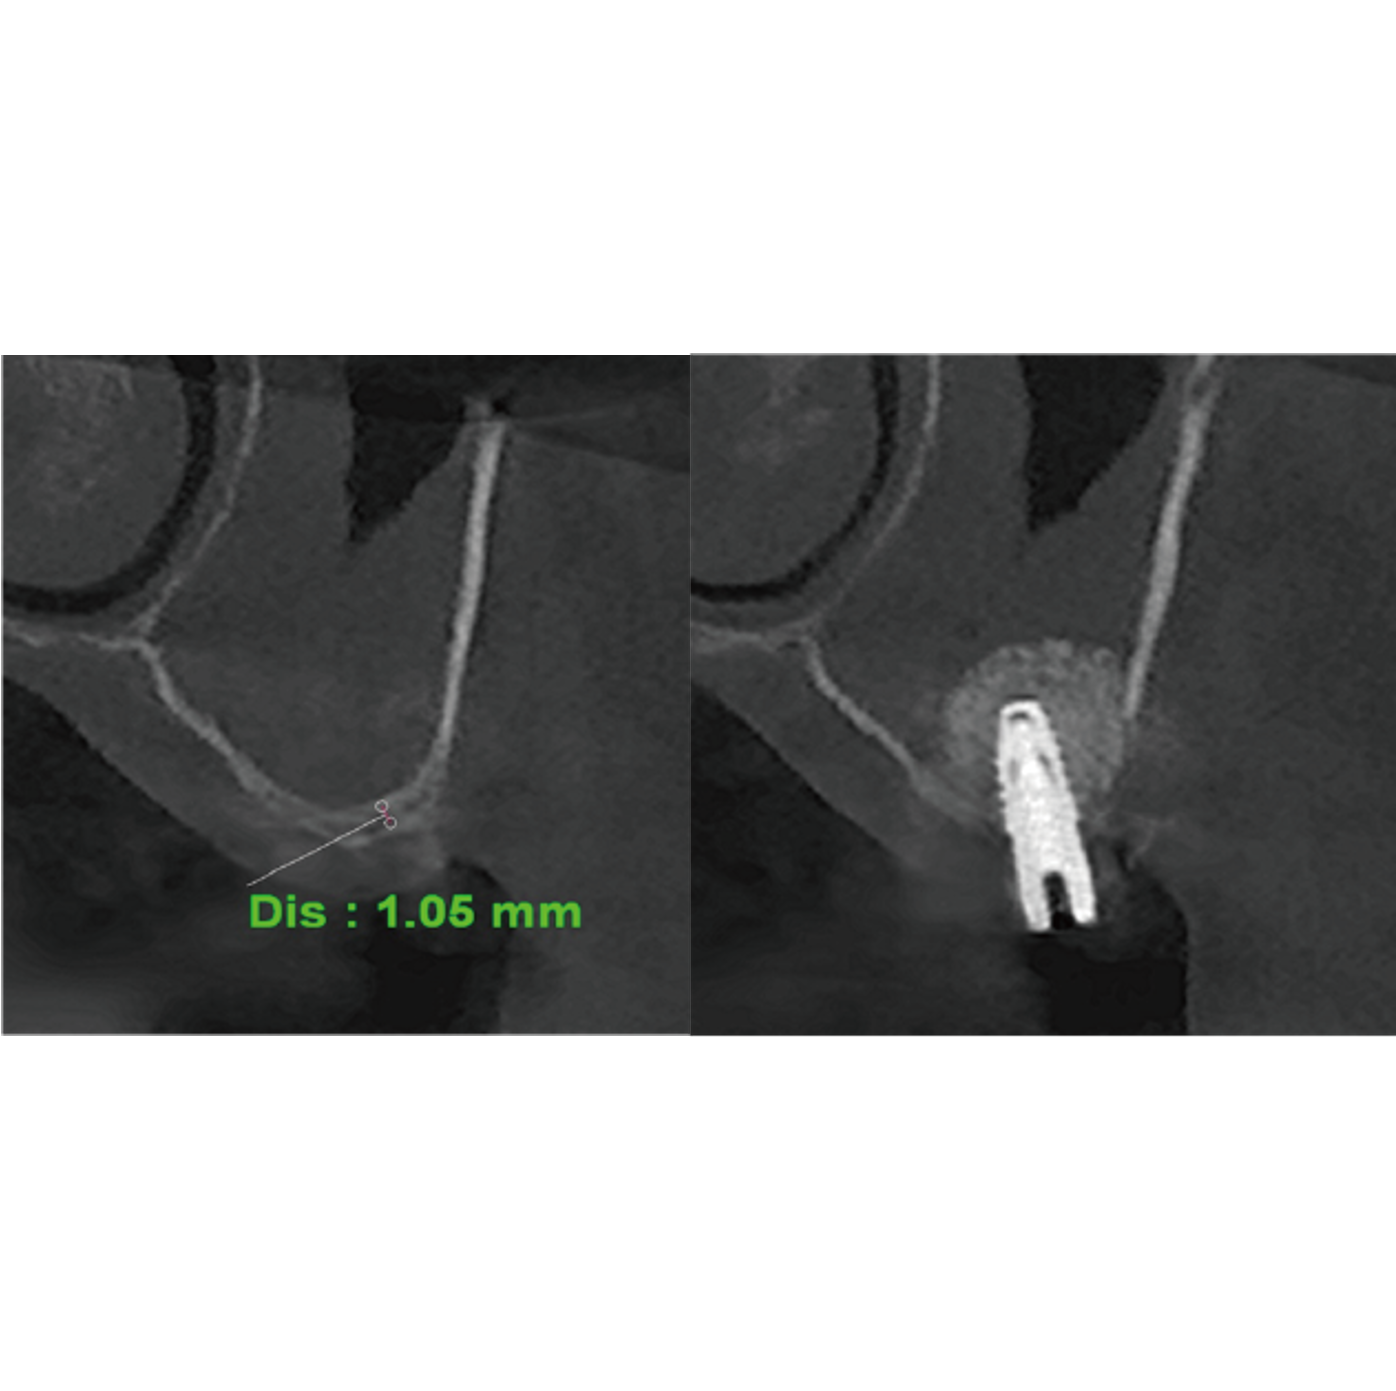

Crestal ApproachAn efficient and safe approach that can serve as an alternative to the conventional lateral approach.

A predictable vertical elevation system minimizes the risk of membrane perforation.

Using a bone spreader, collagen graft material is evenly expanded (tenting) to form a stable dome. -